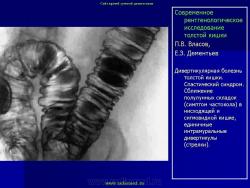

Дивертикулы. Дивертикулярная болезнь.